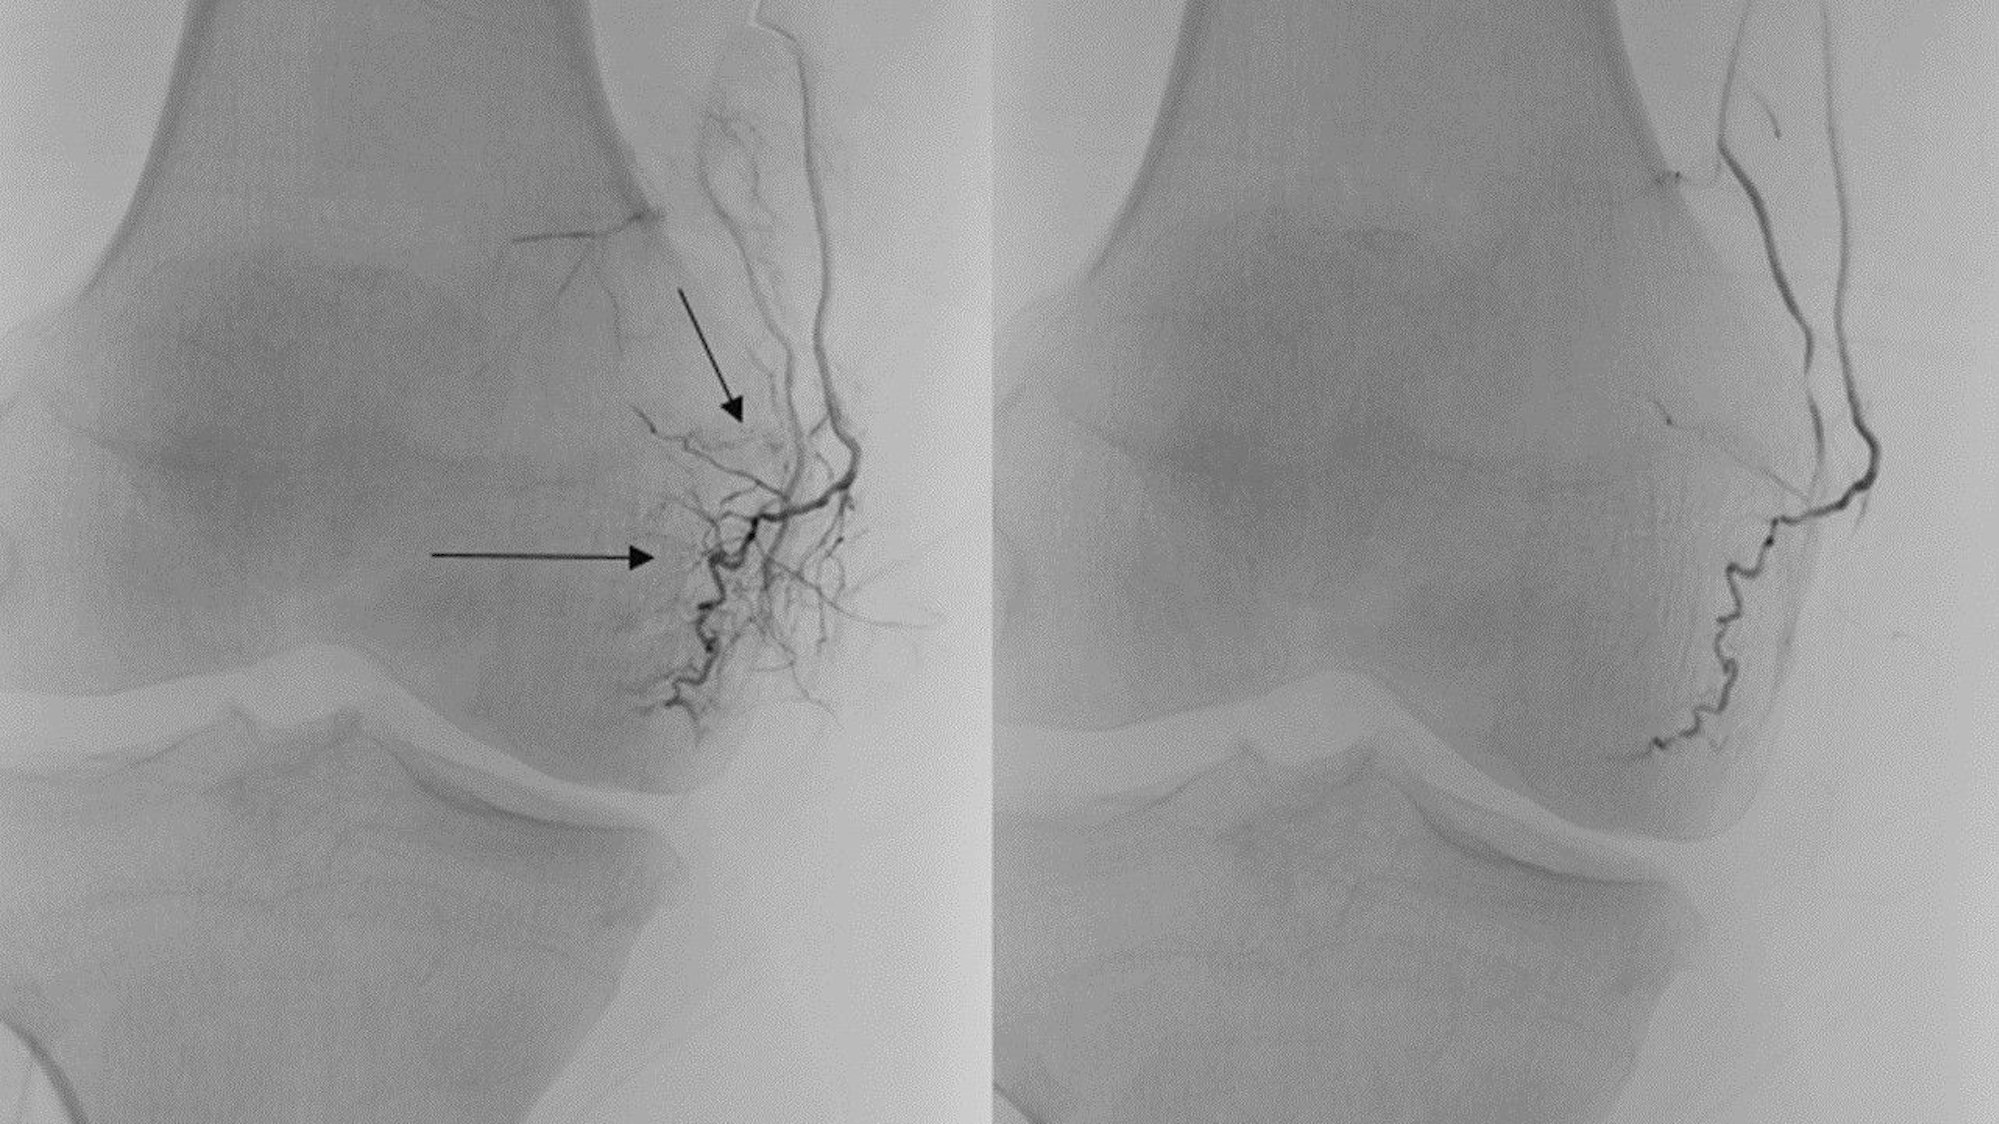

Bei einer TAPE wird die Blutzufuhr zu Entzündungsgewebe unterbrochen. Auf der rechten Seite ist dieser Effekt deutlich zu sehen.

„Wir gehen dabei mit einem wenige Millimeter großen Draht in einem kleinen Katheter durch einen winzigen Zugang in der Arterie in der Leiste in das erkrankte Gelenk“, erklärte Priv.-Doz. Dr. Erkan Celik, Oberarzt in der Interventionellen Radiologie, bei einer Besprechung wenige Minuten vor dem Eingriff an Michael Briese. „Dann suchen wir dort gezielt Bereiche auf, in denen Entzündungen vonstattengehen. Die dort neu entstandenen, krankhaften Arterien schalten wir aus, indem wir ein Medikamentengemisch hineinspritzen.“ Dieses enthalte nicht nur ein Antibiotikum, das die Entzündung hemmt, sondern auch winzige Kristalle, die die Blutzufuhr zu den erkrankten Stellen verstopft.

Der Direktor des Instituts für Radiologie, Univ.-Prof. Dr. David Maintz, stellte zusätzlich klar: „Ich glaube, es ist wichtig zu verstehen, dass nicht die normale Durchblutung gekappt wird, sondern nur die, die darüber hinaus durch die Entzündung pathologisch entstanden ist. Es wird nichts verschlossen, was bei einem gesunden Kniegelenk da ist, sondern es wird immer nur das zugemacht, was darüber hinaus entstanden ist.“

Für den Eingriff wird Briese nur an der Einstichstelle an seiner rechten Leiste betäubt. Dort führen seine Ärzte den Draht ein. Über ihm schwebt ein Röntgengerät, das dem Team auf einem großen Bildschirm live zeigt, wo der Draht hinbewegt wird. Durch ein eingespritztes Kontrastmittel werden die Arterien zuvor sichtbar gemacht. Wie kleine, gräuliche Wolken sehen die entzündeten Stellen aus. Um die krankhaften Arterien „auszuschalten“ hilft Michael Brise dann mit. Er sagt den Ärzten, wo es wehtut und wenn der Schmerz nachgelassen hat. „Also eine Darmspiegelung ist unangenehmer“, sagt er dabei und bringt den ganzen Saal zum Lachen.